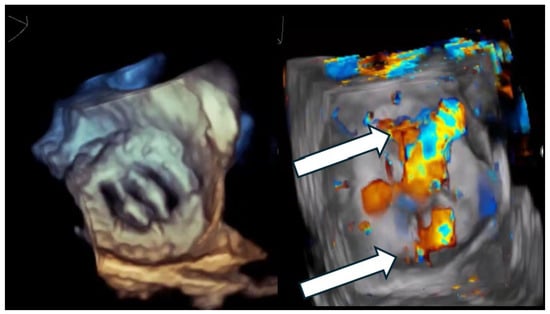

Figure 1.

Multi-orifice (two-hole) paravalvular leak demonstrated by three-dimensional transesophageal echocardiography. (Left panel): Three-dimensional transesophageal echocardiographic en-face reconstruction of the prosthetic valve illustrating the paravalvular region and surrounding annular anatomy. (Right panel): Corresponding three-dimensional color Doppler volume rendering demonstrating two spatially distinct paravalvular regurgitant orifices (arrows) along the prosthetic sewing ring. Each defect generates a separate high-velocity regurgitant jet, confirming the multi-orifice nature of the paravalvular leak rather than a single focal defect.

Figure 2.

Crescentic paravalvular leak with elongated annular involvement. (Left panel): Three-dimensional transesophageal echocardiographic reconstruction of the paravalvular region demonstrating an elongated, crescent-shaped defect extending along the prosthetic sewing ring. (Right panel): En-face three-dimensional view illustrating the continuous, non-circular geometry of the paravalvular channel, with multiple potential exit points distributed along the arc of annular dehiscence.